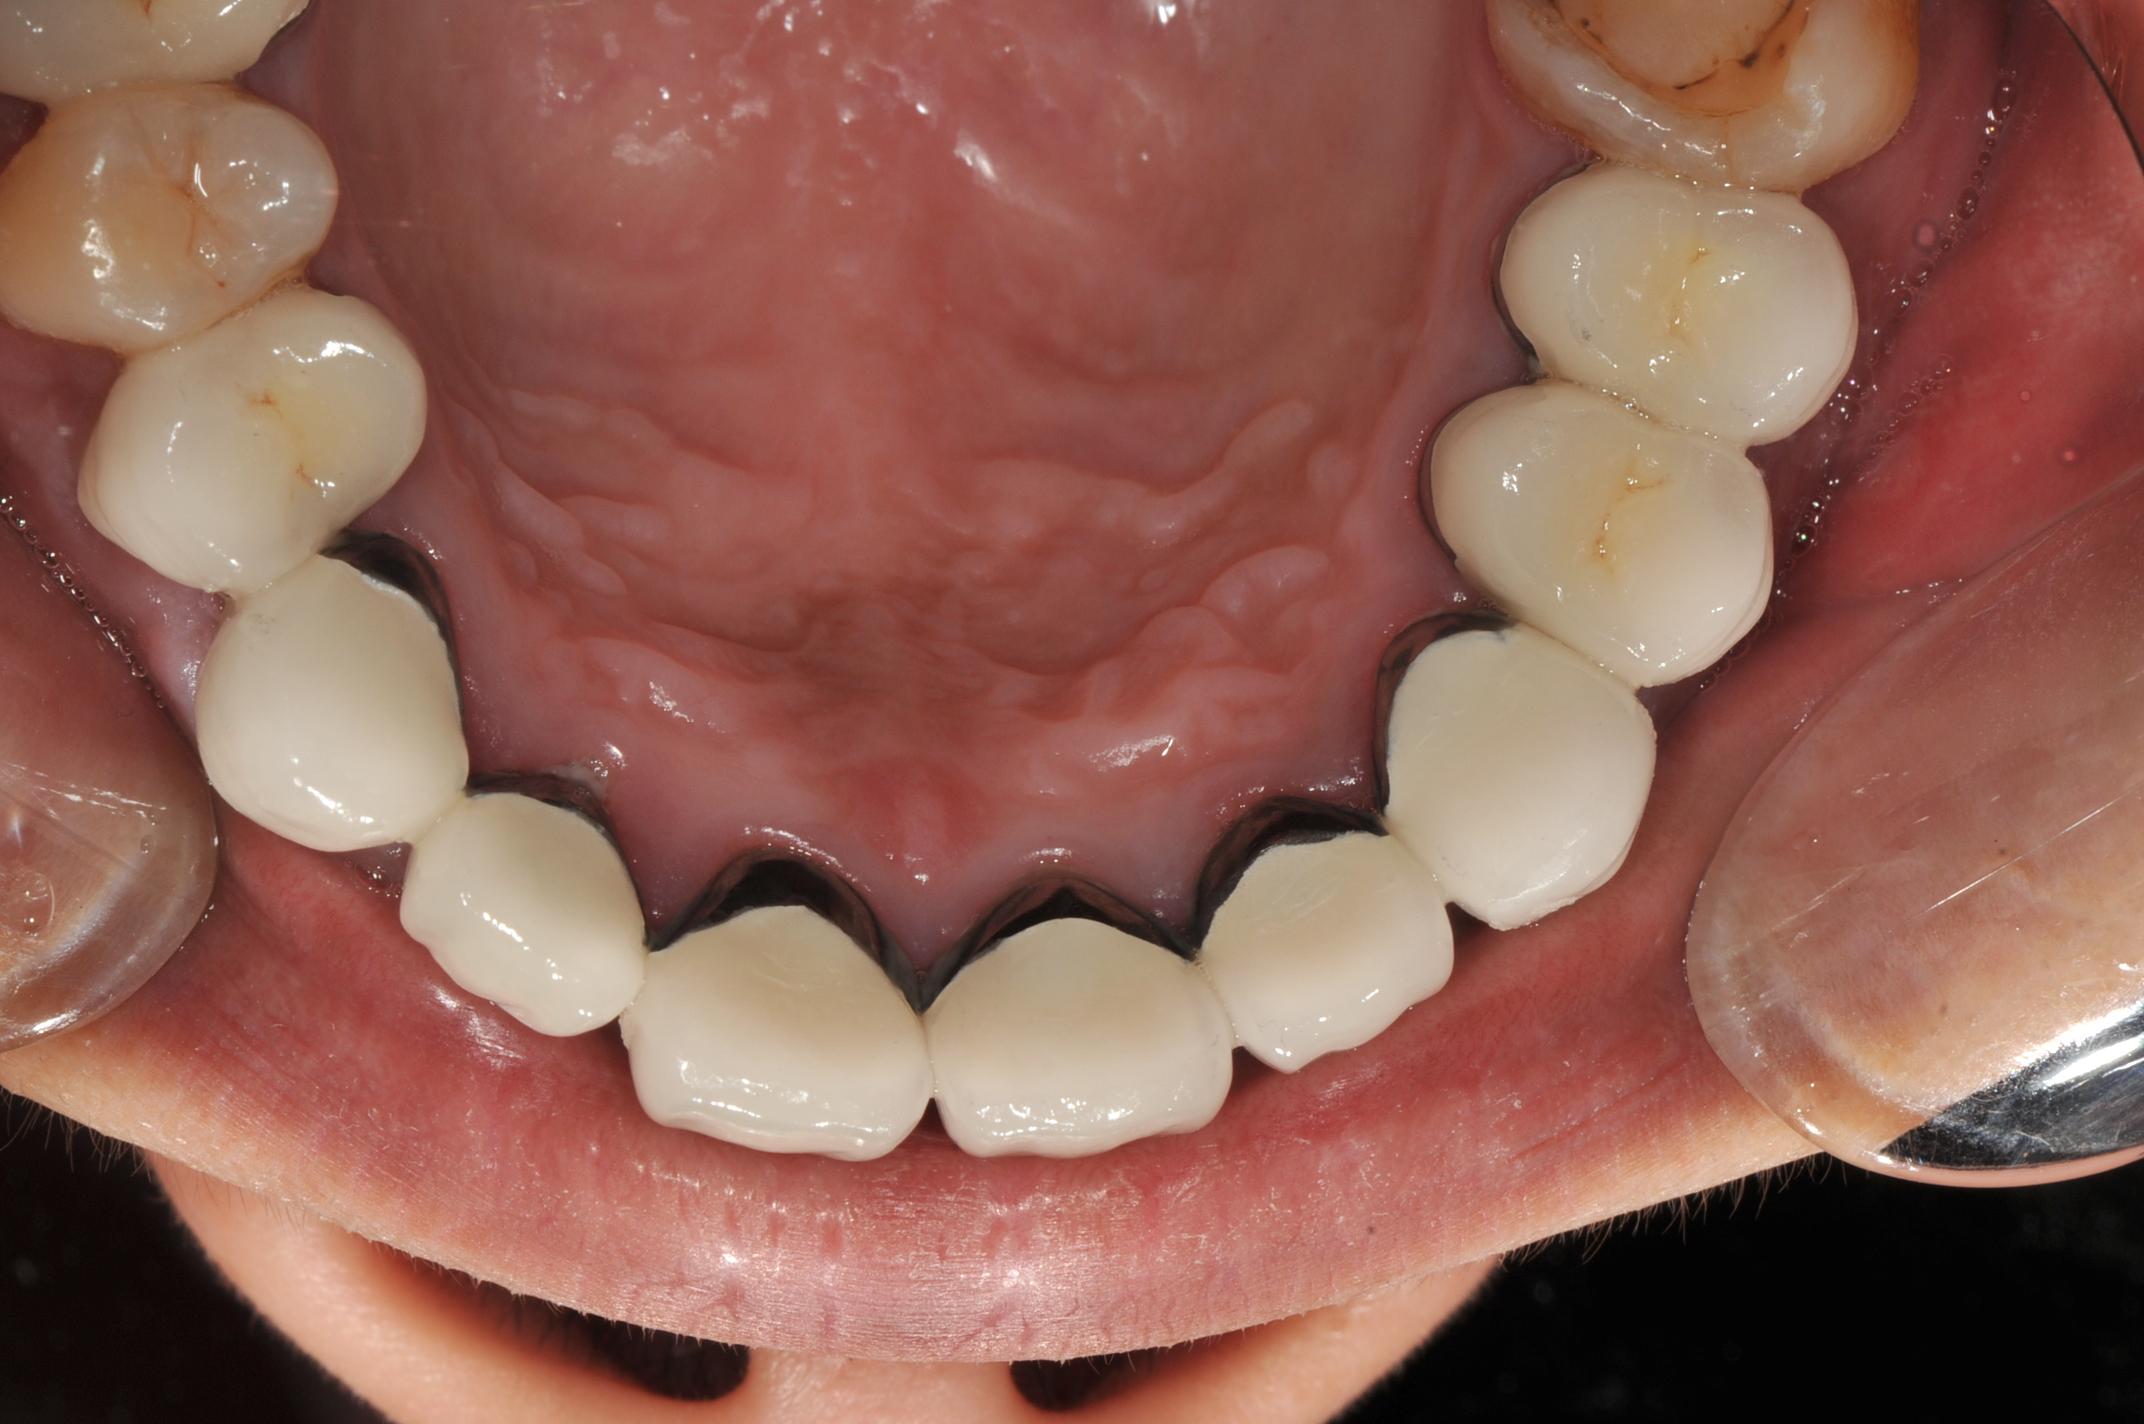

圖九為上頷九顆前牙瓷牙裝戴完成後 , 圖十為咬合面觀

圖十 |